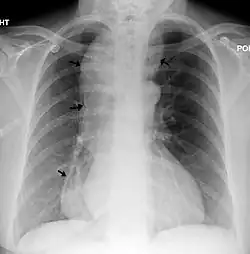

![]() | |

A chest X-ray showing achalasia (arrows point to the outline of the massively dilated esophagus) | |